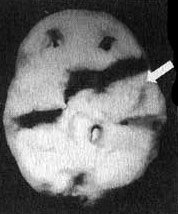

Вместе с Эндрю я отправился в отделение сканирования и, пока проводилось исследование, держал его за руку. Эндрю усадили в кресло, в вену ввели иглу, а через нее — малую дозу радиоизотопов. В это время Эндрю играл на ноутбуке в игру на концентрацию внимания. Через несколько минут иглу вынули, и он пошел в соседний кабинет, где делались снимки. Там его уложили на спину на специальный стол. В течение пятнадцати минут камера, медленно двигавшаяся по окружности вокруг головы Эндрю, производила съемку его мозга. Когда изображение было выведено на экран монитора, я подумал, что в ходе исследования была допущена какая-то ошибка. У Эндрю отсутствовала левая височная доля. Просмотрев все снимки, я убедился, что качество сканирования — хорошее. У него на самом деле не было левой височной доли. Что у него было? Киста? Опухоль? Инсульт? Рассматривая эти снимки на мониторе, я испытывал за него сильный страх. В то же время я чувствовал облегчение от того, что мы установили причину его агрессивности. В своих исследованиях и я, и мои коллеги установили связь между нарушениями в левой височной доле и агрессивностью. На следующий день на магнитно-резонансной томографии мы обнаружили у Эндрю на том месте, где обычно находится левая височная доля, кисту (мешок, заполненный жидкостью), размером с мячик для гольфа. Я знал, что эту кисту надо убрать. Однако поиск специалиста, который серьезно отнесся бы к нашим выводам, оказался трудным.

Отсутствие активности в левой височной доле у Эндрю

Трехмерное изображение нижней поверхности мозга

Иллюстрация к книге — Измените свой мозг - изменится и жизнь! [i_003.jpg]

Нормальный мозг

Иллюстрация к книге — Измените свой мозг - изменится и жизнь! [i_004.jpg]

Мозг Эндрю — левой височной доли не видно